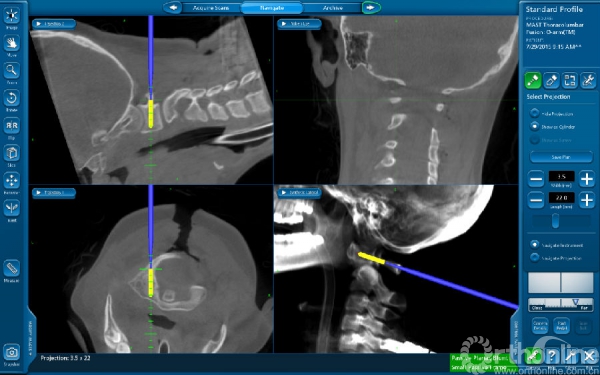

患者杨静(化名)15岁,发现颈椎先天性畸形10余年,持续的多年支具外固定,活动后颈部疼痛,严重影响生活,后慕名到西京骨科医院就诊。入院后由桑宏勋副主任为其进行了全面病情评估,发现患者寰枢椎畸形严重,并伴有椎动脉高跨,病情复杂手术风险大,经过科室讨论决定为其实施“导航辅助下寰枢椎脱位复位、椎弓根螺钉内固定、植骨融合术”。术中利用O-arm扫描获得患者实时影像数据,导入导航系统进行三维重建后进行精准的置钉、复位等手术操作。相对于传统手术方式,O-arm联合导航系统可以使手术操作可视化、精准化,减少手术时间与术中出血量,降低患者手术风险。术后患者恢复良好并已康复出院。

术中影像图片